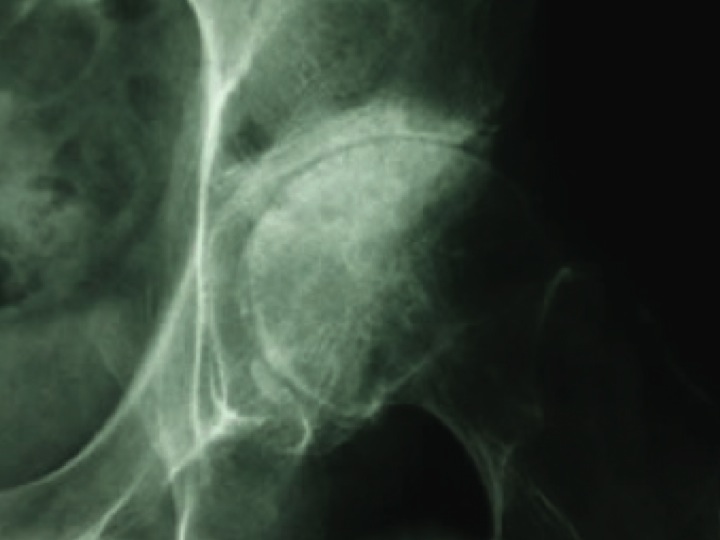

Hip Osteoarthritis Background

Hip Osteoarthritis (OA) is considered one of the most serious musculoskeletal problems secondary to its impact on patients’ pain and disability, as well as, the economic impact on our healthcare system.

20% of the aging population will experience hip OA and the condition is a predictor of current and future func- tional disability and mortality(1,2).

Only 20% of patients with hip OA on x ray testing will end up having a total hip replacement 11-28 years after diag- nosis. Quality conservative care is crucial for this population(3).